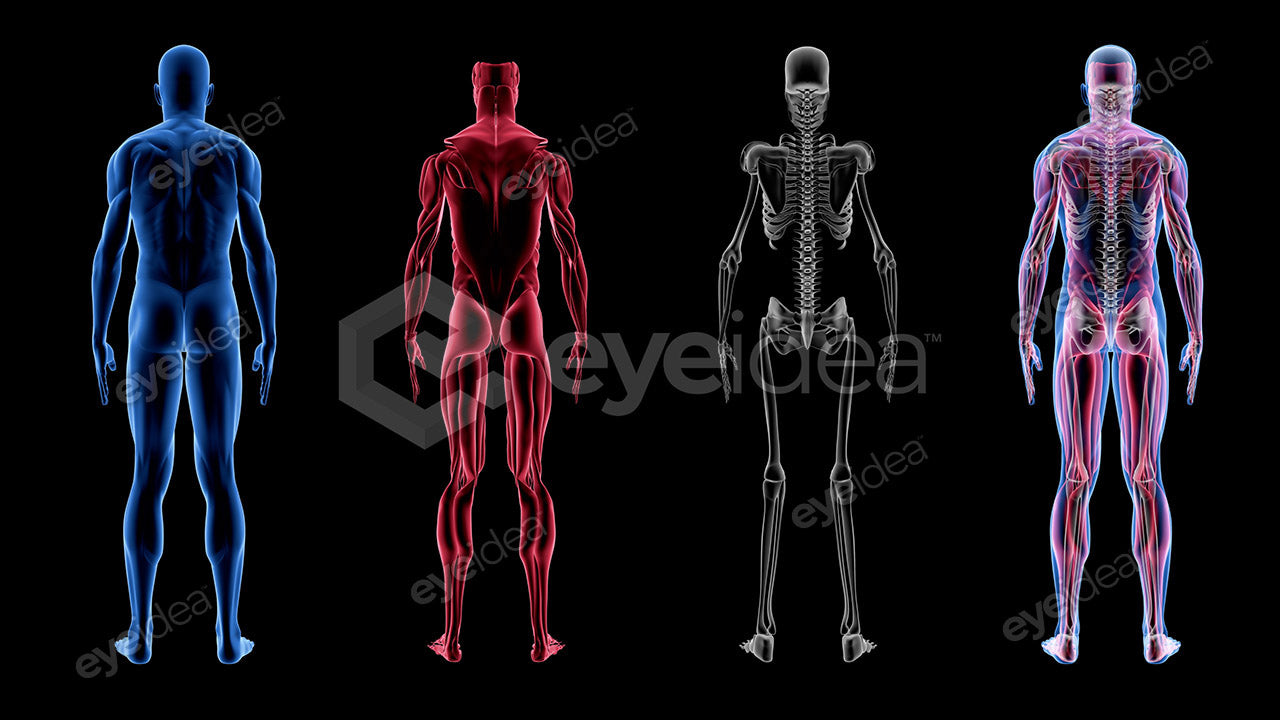

Versatility and Variety

Our Stock-Packs™ are curated to include a varied

range of angles, motion, styles and formats,

ensuring that creators can find the assets

they want fast and easy.